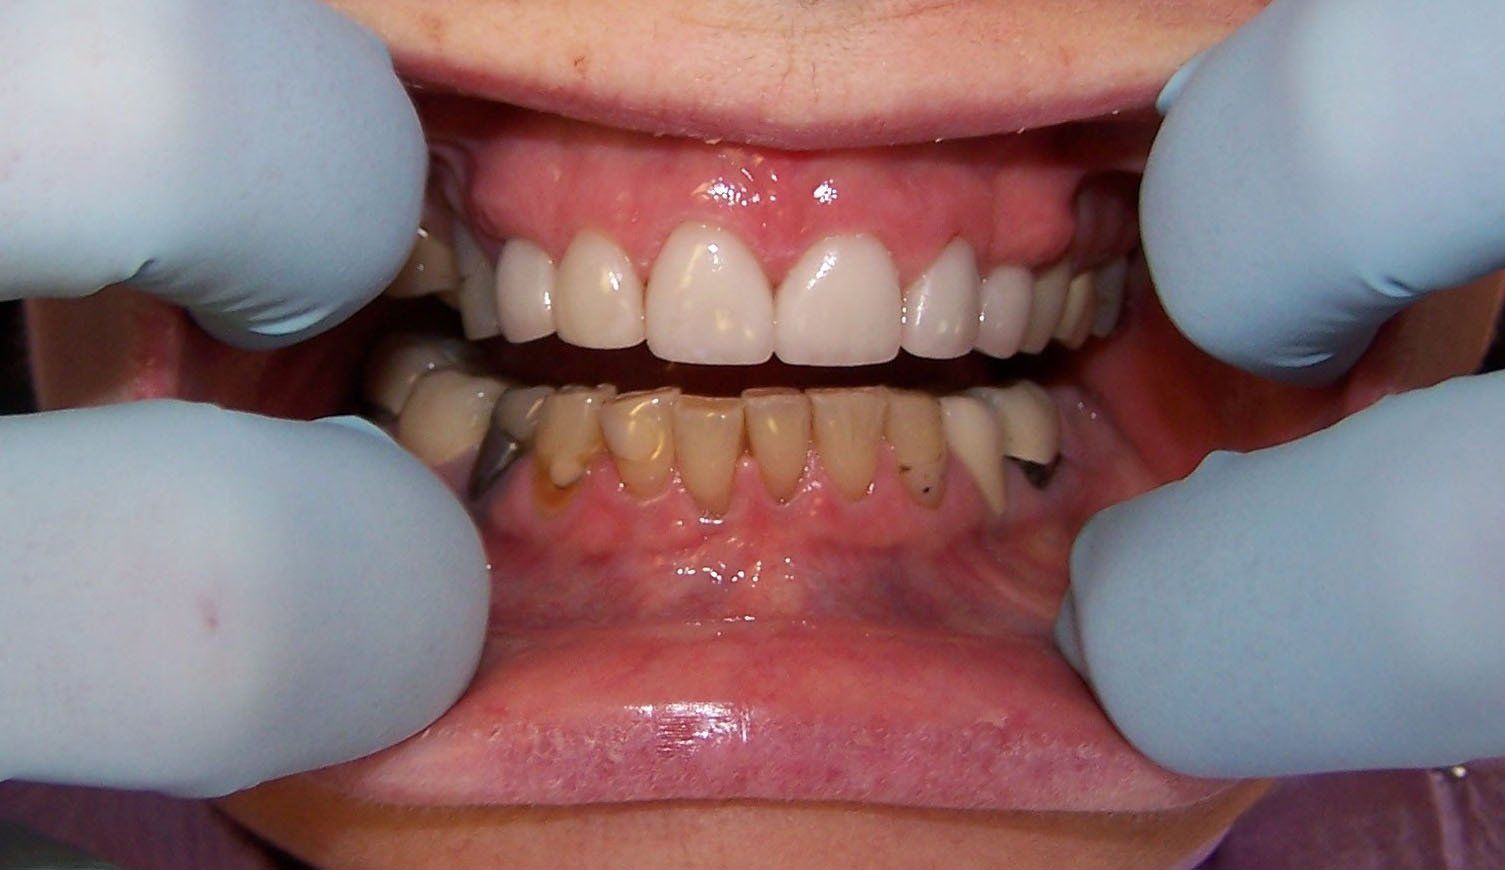

Holly After

Button